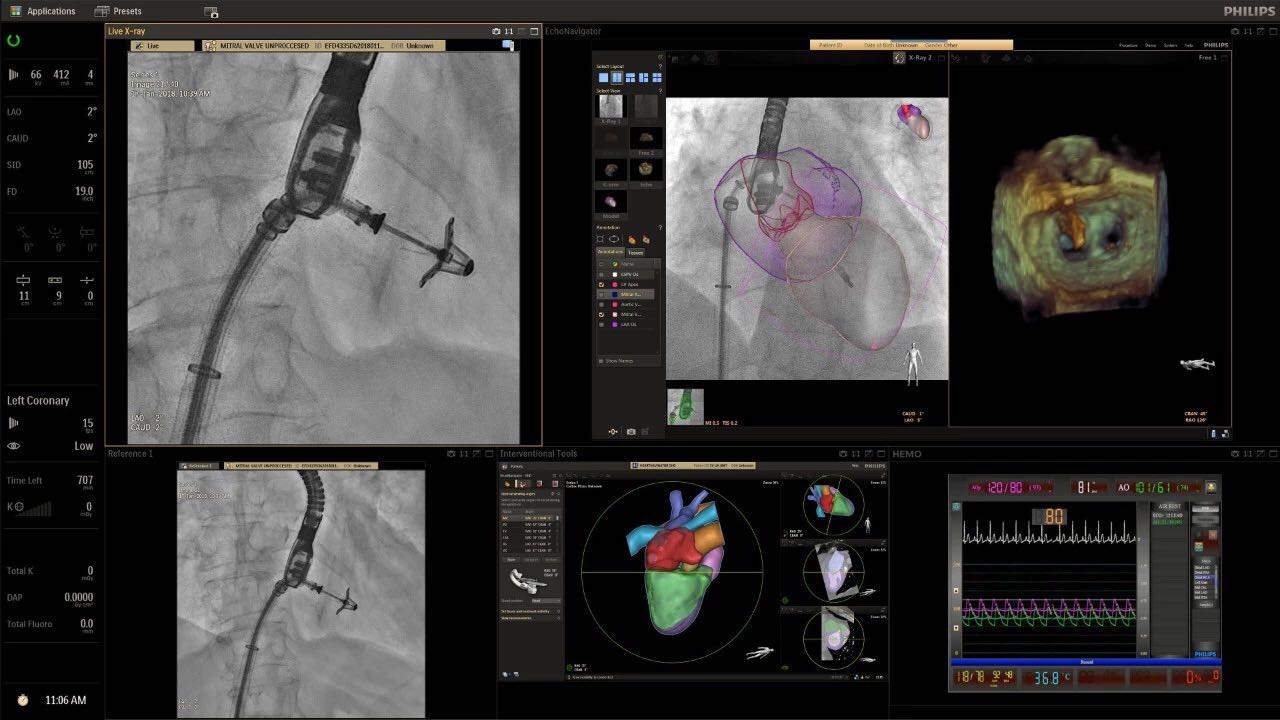

在日益復(fù)雜的干預(yù)期間,臨床醫(yī)生需要快速、輕松地可視化關(guān)鍵解剖結(jié)構(gòu)并確定手術(shù)過(guò)程中患者的變化。2019年1月17日,飛利浦宣布推出采用FlexArm的Azurion 7 C20,旨在提高圖像引導(dǎo)程序的定位靈活性。

可通過(guò)微創(chuàng)手術(shù)治療的疾病的范圍和復(fù)雜性繼續(xù)擴(kuò)大。相應(yīng)地,程序本身也變得更加復(fù)雜,需要來(lái)自不同學(xué)科的更多醫(yī)生在患者的桌邊,以高度協(xié)調(diào)的方式一起工作。因此,臨床團(tuán)隊(duì)需要在高度受限的環(huán)境中執(zhí)行越來(lái)越具有挑戰(zhàn)性的程序。

飛利浦表示,采用FlexArm設(shè)計(jì)的Azurion 7 C20可提供卓越的靈活性和直觀的控制。該系統(tǒng)由智能運(yùn)動(dòng)引擎驅(qū)動(dòng),可在八個(gè)不同的軸上移動(dòng),所有這些軸均由其單個(gè)“Axsys”控制器控制。臨床醫(yī)生的模擬測(cè)試表明,該系統(tǒng)有可能顯著減少患者,工作人員和設(shè)備的重新定位,從而改善微創(chuàng)手術(shù)的可及性,包括通過(guò)患者手腕進(jìn)入身體的手術(shù)(橈動(dòng)脈入路),并降低患者的風(fēng)險(xiǎn)。無(wú)意中拔出電線和管子,以及節(jié)省大量時(shí)間。該系統(tǒng)非常適合混合手術(shù)室(OR),可滿足一個(gè)房間內(nèi)的多種專業(yè)需求,例如手術(shù)和血管內(nèi)手術(shù)的組合。